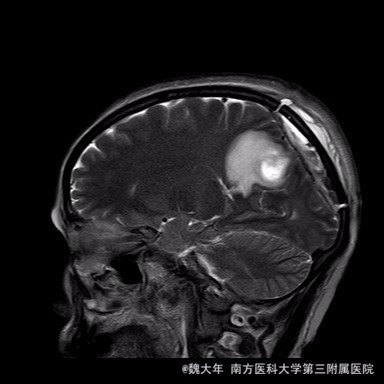

52岁,女性,因“反复头痛10余年,加重1年”入院。患者10余年前无明显诱因始出现头痛,表现为全头发作性胀痛,反复发作,无伴头晕、恶心,无呕吐、肢体抽搐,自行服药(具体不详)及休息后缓解,未予特殊处理。1年前患者觉头痛逐渐加重,以右顶部为甚,劳累或日晒后加重,无头晕、视物旋转,无恶心、呕吐,无发热、寒战,休息或平躺后症状稍有缓解,自行服药不能改善,至当地医院就诊,查颅脑MRI和CT提示“右侧顶部脑膜瘤”。

行“右顶开颅右顶部矢状窦旁脑膜瘤切除术”。取右顶马蹄形手术切口 ,颞侧翻开皮瓣,电刀切开骨膜,中线矢状缝上前、后极各钻一孔,颞侧后方钻一孔,铣刀铣一长方形(7*6cm)骨瓣,见硬膜表面较多点状渗血,予充分止血,悬吊硬膜。 显微镜下切除肿瘤:沿肿瘤边缘剪开硬膜后,见一大小约5*5*6cm肿瘤,沿硬膜内侧面呈匍匐状生长,边界与脑组织有蛛网膜分隔,质地较韧,基底与矢状窦关系密切,靠内侧与大脑镰粘连紧密,血供丰富。仔细分离肿瘤与脑组织的粘连,全切除肿瘤。肿瘤基底与矢窦粘连紧密,并破坏矢状窦侧壁,予低功率电刀反复烧灼,直至肿瘤无明显血供表现。严密止血后常规关颅。

术后1周复查头颅MR未见明显肿瘤残留,拆线后出院。